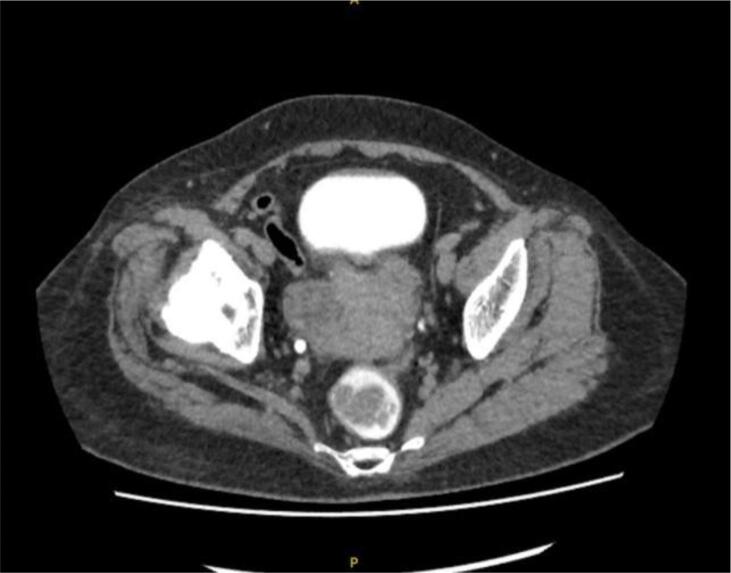

A 68-year-old Chinese woman was diagnosed with Stage IVB ULMS (spindle type) with lung metastasis in January 2021. Initial computed tomography (CT) revealed a uterine mass measuring 7.5 x 6.3x 5 cm (Fig. 2A), and multiple lung metastases (Fig. 2B). She underwent total abdominal hysterectomy with bilateral salpingo-oophorectomy (TAHBSO) and omentectomy in January 2021. Histopathological report revealed the tumour to be a malignant uterine tumour involving the myometrium, consisting of predominantly malignant spindle cells. Immunohistochemistry (IHC) report confirmed a profile consistent with ULMS. Estrogen Receptor/Progesterone Receptor negative. The patient was started on first line palliative chemotherapy: Gemcitabine and Docetaxel. She completed 6 cycles of this regimen in July 2021. CT reassessment at this point showed stable lung lesions (Fig. 2C). Following a one-month treatment break, CT imaging revealed an increase in size of the lung lesions, with no new lesions. The patient was then started on Pazopanib 800 mg OD. This was stopped after 3 months, due to treatment toxicity - Hand-Foot-Syndrome (HFS), associated with transaminitis and proteinuria. The patient was then started on Eribulin as third line treatment. She remained on this for 4 months until June 2022. CT imaging revealed disease progression, with new enhancing lesions suggestive of right-sided abdominopelvic recurrence and worsening lung and pleural base metastases (largest measuring 3.3x5.2x7.7 cm, previously 1.9x2.5x2.7 cm). The patient’s regimen was then changed to Doxorubicin and Cyclophosphamide. Although there is no universally accepted sequence of palliative chemotherapeutic agents, doxorubicin with cyclophosphamide is often attempted as first or second-line treatment. This was avoided in an early-line setting in this case to minimise the risk of cardiac toxicity. After 4 cycles of this regimen in September 2022, CT revealed further disease progression with increasing abdominopelvic enhancing recurrence, worsening lung and pleural-based metastases and liver metastases (Fig. 2D).

Fig. 2A.

Uterine mass.

Fig. 2D.

Post Doxorubicin + Cyclophosphamide + Docetaxel.

In view of PD-L1 status of the tumour, she was started on immune checkpoint blockade. The decision was made to start on combination of pembrolizumab 200 mg, 4 weekly and temozolomide 300 mg D1-5, 4 weekly. CT after completion of cycle 4 revealed a reduction in right abdominopelvic mass size (3.4x2.2x2.4 cm, previously 7.2x5.2x5.6 cm), lung and pleural-based metastases (1.3x3.6x3.1 cm, previously 3.3x6.0x7.7 cm)(Fig. 2E). She was continued on the current regimen and is now on cycle 7. Patient has tolerated this regimen well throughout all cycles with minimal toxicity (Fig. 1).

Fig. 2E.

Response post Pembrolizumab + Temozolomide.